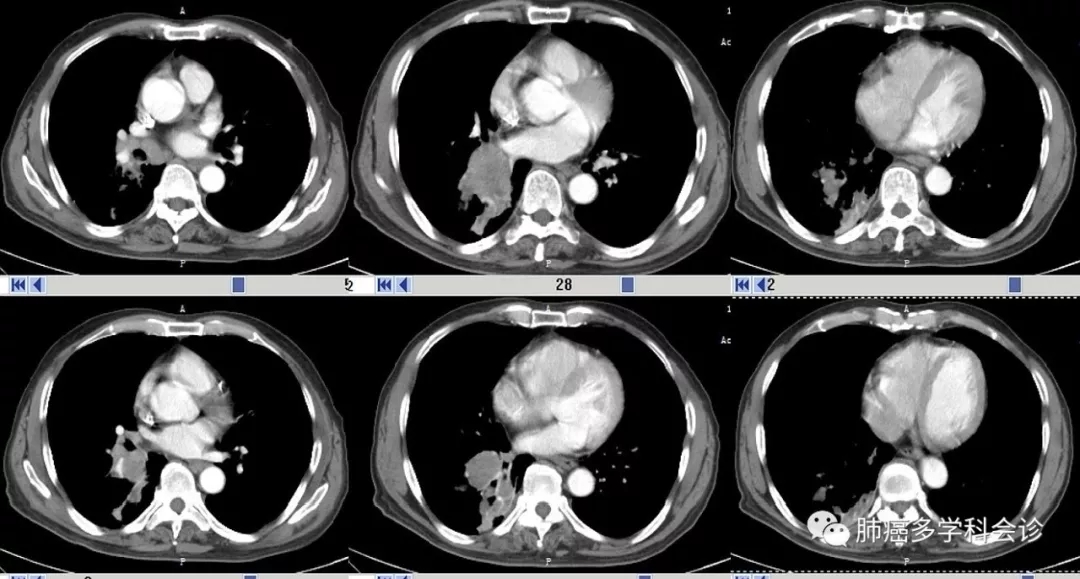

给予 “安罗替尼”单药口服 2 周期,复查CT示胸水略减少,肝转移灶大小没有明显变化。

患者参加我们的肺癌多学科会诊。专家组建议:完善基因检查(女性肺鳞癌),尝试纳武利尤或其他PD-1抗体免疫治疗。也可考虑在安罗替尼基础上联合PD-1抗体

5.webp.jpg